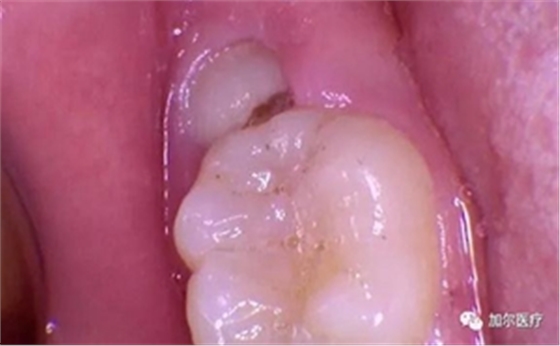

嘴里無(wú)緣無(wú)故多了兩顆智齒,橫著長(zhǎng)偶爾來(lái)幾次發(fā)炎腫痛,后來(lái)找了牙醫(yī)拍片檢查,以為拔除這過(guò)程會(huì)特別痛苦,結(jié)果牙醫(yī)并沒(méi)有直接拔除,還留了一顆下次拔,但奇怪的是為什么不是拔而是切智齒?

實(shí)際上拔智齒不是真的拔你智齒,以前是用錘子拔,現(xiàn)在是微創(chuàng)拔牙技術(shù)講究切,這樣做是為了減少創(chuàng)傷,一般切開(kāi)牙齦后,鉆掉小部分顎骨,先切掉取出牙冠部分,再將牙根切成兩半,逐一取出根部,通常智齒半個(gè)鐘左右拔完,而且不能一下子拔兩顆,除非是上下頜智齒,同時(shí)也得考慮到自身體質(zhì)。